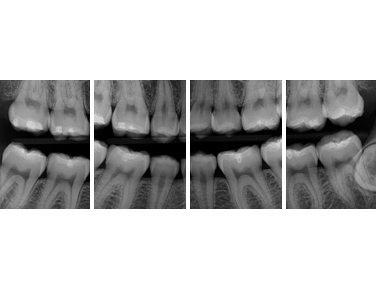

For the first time in the 100-year history of dental X-rays (radiography), an extraordinary new technology surpasses the diagnostic abilities of traditional film. It does so with substantially less radiation exposure to you.. and us. This system has truly amazing diagnostic tools, making the image quality simply unmatched.

Lockheed Martin, the aerospace manufacturer of the Magellan Venus Spacecraft and the Hubble Telescope designed the digital X-ray sensor that is the heart of this technology. The sensor is very special as it has a uniquely shaped design for your optimum comfort. No more sharp edges like the old film had. This allows for increased positioning accuracy.

This system allows for the ability to instantly produce the very best possible diagnosis and produces up to 90% less radiation.